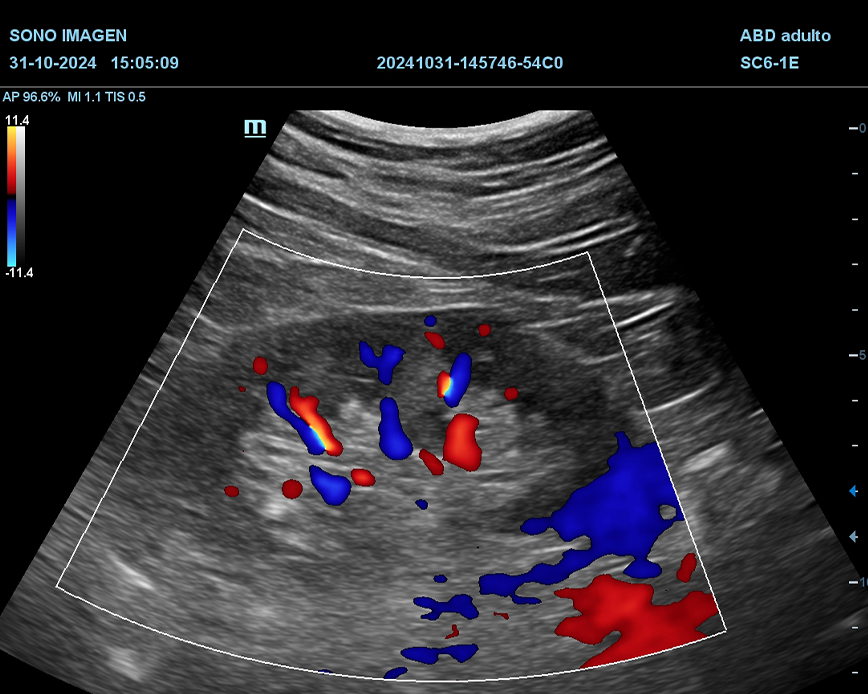

Ecografía Prostática

- hiperplasia prostática benigna(HPB)

- cáncer de próstata

- prostatitis

- dificultad para orinar o retención urinaria

- hematuria

- alteraciones en la fertilidad masculina

- control postquirúrgico o postratamiento

- anomalías detectadas en estudios previos

- quistes prostáticos